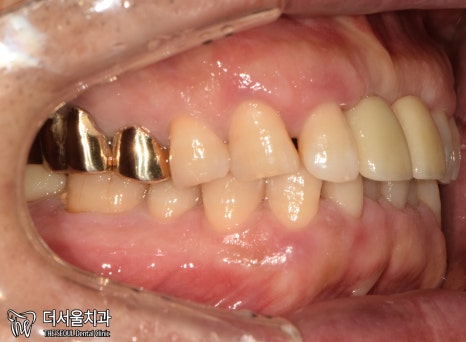

1. 구강 체크

현충일 공휴일 정상진료

서현역 치과를 찾아오셨던 환자분은

앞니와 왼쪽 끝 어금니에

이상 증세를 느껴 찾아오셨습니다.

겉으로 봤을 때는 큰 문제는 없는 것처럼 보입니다.

그럼 대체 무슨 문제가 있는 걸까요?

겉으로 보여지는 것이 아닌,

속을 들여봐야 알 수 잇겠네요.

엑스레이 촬영을 통해 체크해보겠습니다.